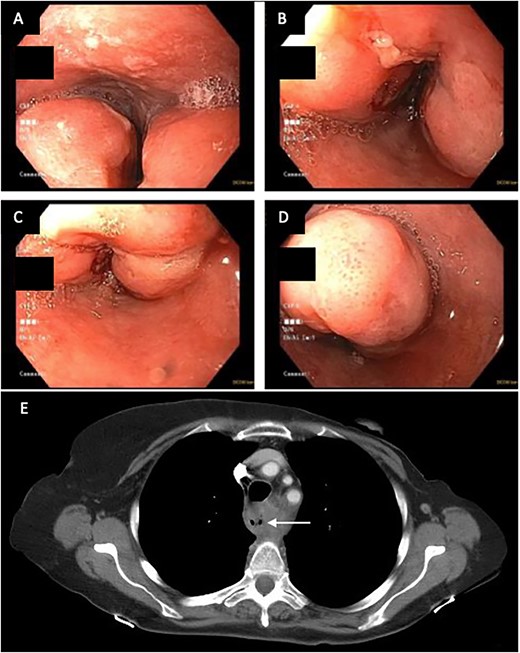

(A) CT image from January 2021 showing severe narrowing of the lumen of the esophagus proximal to the stent. (B) EDG from February2021 showing response to balloon dilation of a stricture proximal to the indwelling stent.

Palliative supports for the patient were arranged. CT scan at this time (January 2021, Fig. 2A) showed severe luminal narrowing of the esophagus proximal to the stent. The patient initially declined a feeding gastrostomy tube to avoid further aspiration. Instead, repeat EGD with balloon dilatations were performed to relieve dysphagia (Fig. 2B). TEF was still not detected on bronchoscopy or on barium esophagogram. The patient continued to have recurrent pulmonary infections treated with oral antibiotics. In April 2021, a percutaneous endoscopic gastrostomy tube was inserted to facilitate enteral nutrition and minimize aspiration.